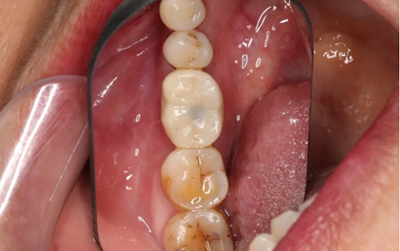

18、最終修復(fù)(口腔照片)

常規(guī)制作全瓷冠,試戴合適,粘接固位。

(攝于2018年6月13日)

常規(guī)制作全瓷冠,試戴合適。